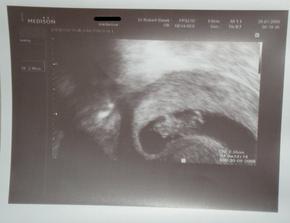

26/1 - tak máme za sebou kontrolu, mimísovi se daří dobře, máme 21,6 mm, jsme 8+4 a podle UTZ 9+1... a dostali jsme průkazku!!!! Pan doktor říkal, že teďka už to bude dobrý, že to úplně nejhorší už áme za sebou... Jinak další kontrola bude až 23/2, tak to se asi nedočkám... a prý rovnou uděláme genetický screening... no přeci jen už budu ve 13. týdnu....